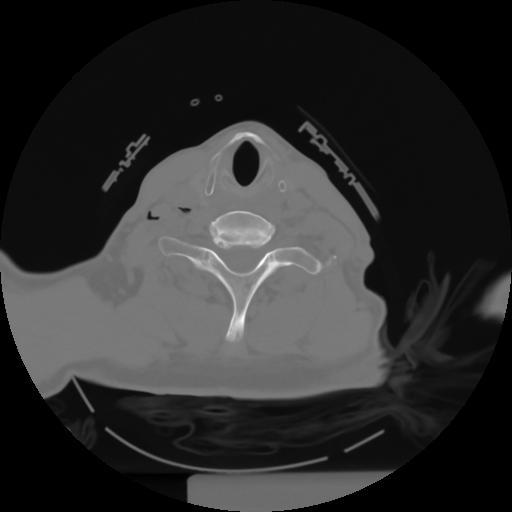

10 P.BLANDAS,,Axial,2.0,P.BLANDAS,,